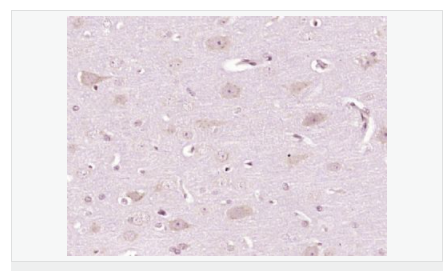

| 產(chǎn)品介紹 | This gene encodes a member of a small calcium-binding EF-hand protein family. The encoded protein is thought to have a key role in Golgi calcium homeostasis and Ca(2+)-regulated signal transduction events. [provided by RefSeq, Jun 2010] Function: Major calcium-binding protein of the Golgi. May have a role in calcium homeostasis. Subcellular Location: Golgi apparatus > cis-Golgi network membrane. Cytoplasm. A small fraction of the protein may be cytoplasmic. Tissue Specificity: Expressed both in fetal and adult heart, lung, liver, kidney and brain, and in adult skeletal muscle, placenta and pancreas. Post-translational modifications: Phosphorylated upon DNA damage, probably by ATM or ATR. Similarity: Belongs to the nucleobindin family. Contains 2 EF-hand domains. SWISS: Q02818 Gene ID: 4924 Database links: Entrez Gene: 4924 Human Entrez Gene: 18220 Mouse Omim: 601323 Human SwissProt: Q02818 Human SwissProt: Q02819 Mouse Unigene: 631602 Human Unigene: 258923 Mouse Unigene: 1492 Rat Important Note: This product as supplied is intended for research use only, not for use in human, therapeutic or diagnostic applications. |